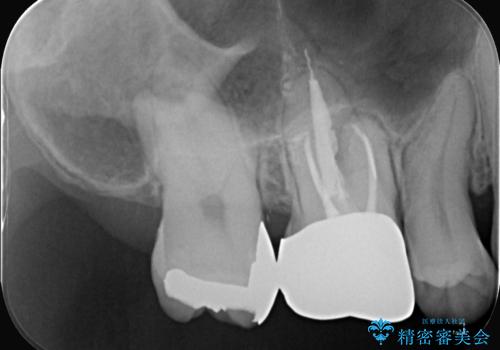

右上6番目の歯の被せものと歯質の境目に大きな窪みが出来ており、そこに汚れが停滞しやすい状態で虫歯もそこから広がっていたため、被せもののやり替えと必要に応じて土台の立て直しも行うこととしました。

メタルクラウンを除去したところ近心面に大きな窪みとう蝕を認め、ファイバ-コアからのやり替えとしました。クラウンは審美性の良いセラミッククラウンを選択されました。